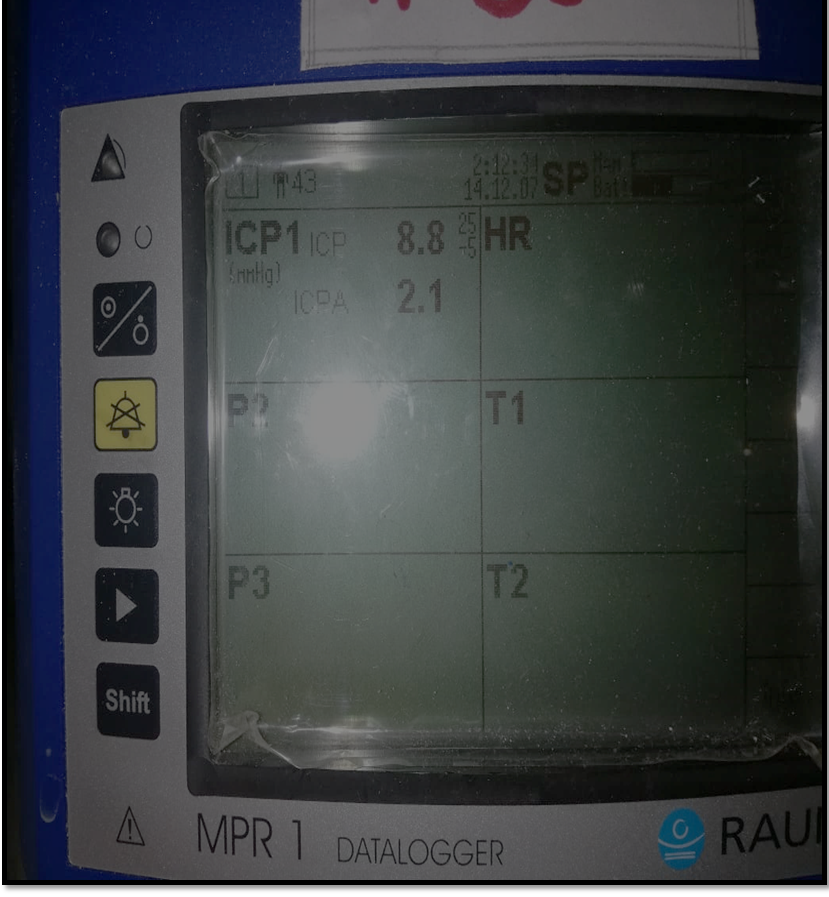

As durotomy is done, both ICP and ICP A again plummet to the normal values, also evidenced by the graph.